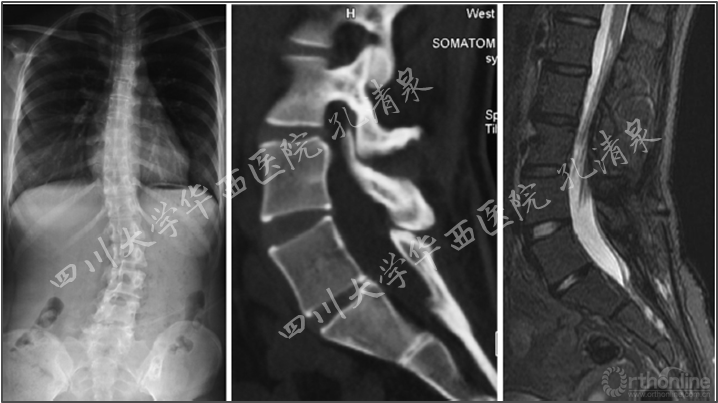

图8 腰椎正位像上示多节段腰椎右侧横突骨折,腰骶部侧凸,CT矢状面重建示腰5椎IV°滑脱,腰5骶1椎间盘完好,骶1前上缘骨骺向前滑移

诊断:1. 腰5创伤性IV°滑脱并骶1骨骺损伤伴脊柱侧凸(SDSG 5型)

2. 腰1-4右侧横突骨折